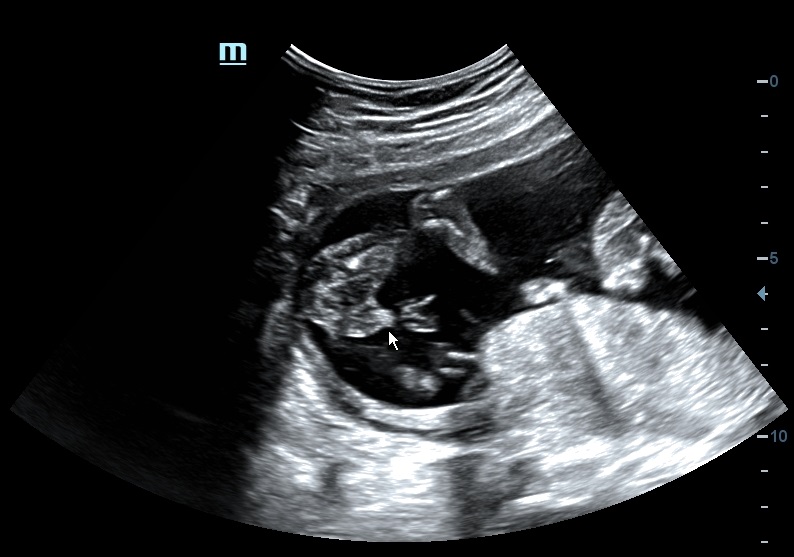

Can someone confirmed with this photo? is this baby boy or baby girl?

Maybe girl

Looks girly, but at a very odd angle for a potty shot. Could be a boy as well with the boy bits hiding. I am no help. Sorry.

I assume this is a boy then. I was just guessing, it's a bad potty shot. Do you have any other pics?

i will try to locate any other photo. but so far this is the photo that the tech said making him say is a boy.